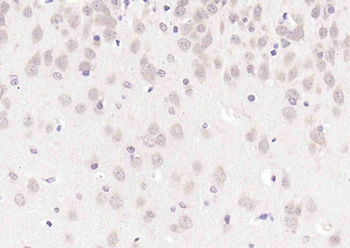

CDKN1A Antibody

Catalog Number: orb682382

| Description | CDKN1A Antibody |

| Target | CDKN1A |

200 μl, 50 μl, 100 μlCDKN1A/p21 Rabbit Polyclonal Antibody [orb11203]

FC, ICC, IF, IHC-Fr, IHC-P

Bovine, Canine, Gallus

Human, Mouse, Rat

Rabbit

Polyclonal

Unconjugated

50 μl, 100 μl, 200 μlPhospho-PAK6 (Ser560) Rabbit Polyclonal Antibody [orb6634]